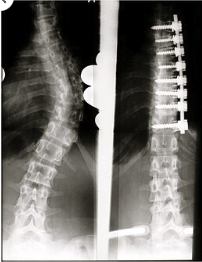

During fusion surgery, rods and screws are used to straighten and stabilize the spine, and bone grafts are placed to fuse vertebrae together. While the surgery can reduce curvature and prevent progression, it comes with risks: limited mobility in the fused area, a long recovery time, and potential for complications down the line.

A newish surgical option is vertebral body tethering (VBT) used to treat scoliosis in children who are still growing, and have curves between 30-50°.

Screws are inserted into the vertebral bodies along the outer curve of the spine and a flexible cord, or tether is then attached to the screws and partially straightens the curvature. As the child grows, the tension on the tether encourages the spine to straighten further.